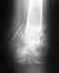

Здравствуйте. Попал в ДТП, произошло расхождение лонного сочленения, был прооперирован, симфиз закреплен двумя пластинами, спереди и сверху.

Посмотрите пожалуйста снимок, не велико ли расстояние в лонном сочленении после операции? Ведь вроде должно быть 5-6 мм. И если велико, то как это повлияет на меня в дальнейшем? Сейчас хожу на костылях. Срок после операции полтора месяца. Заранее большое спасибо за ответ!

Действительно, есть значимое расхождение. Оно говорит о повреждении и неустраненном смещении в задних отделах таза. На снимке этот отдел срезан.

В диагностике помогут снимки с захватом их (прямой и inlet) и КТ. Вероятно, придется делать еще одну операцию.